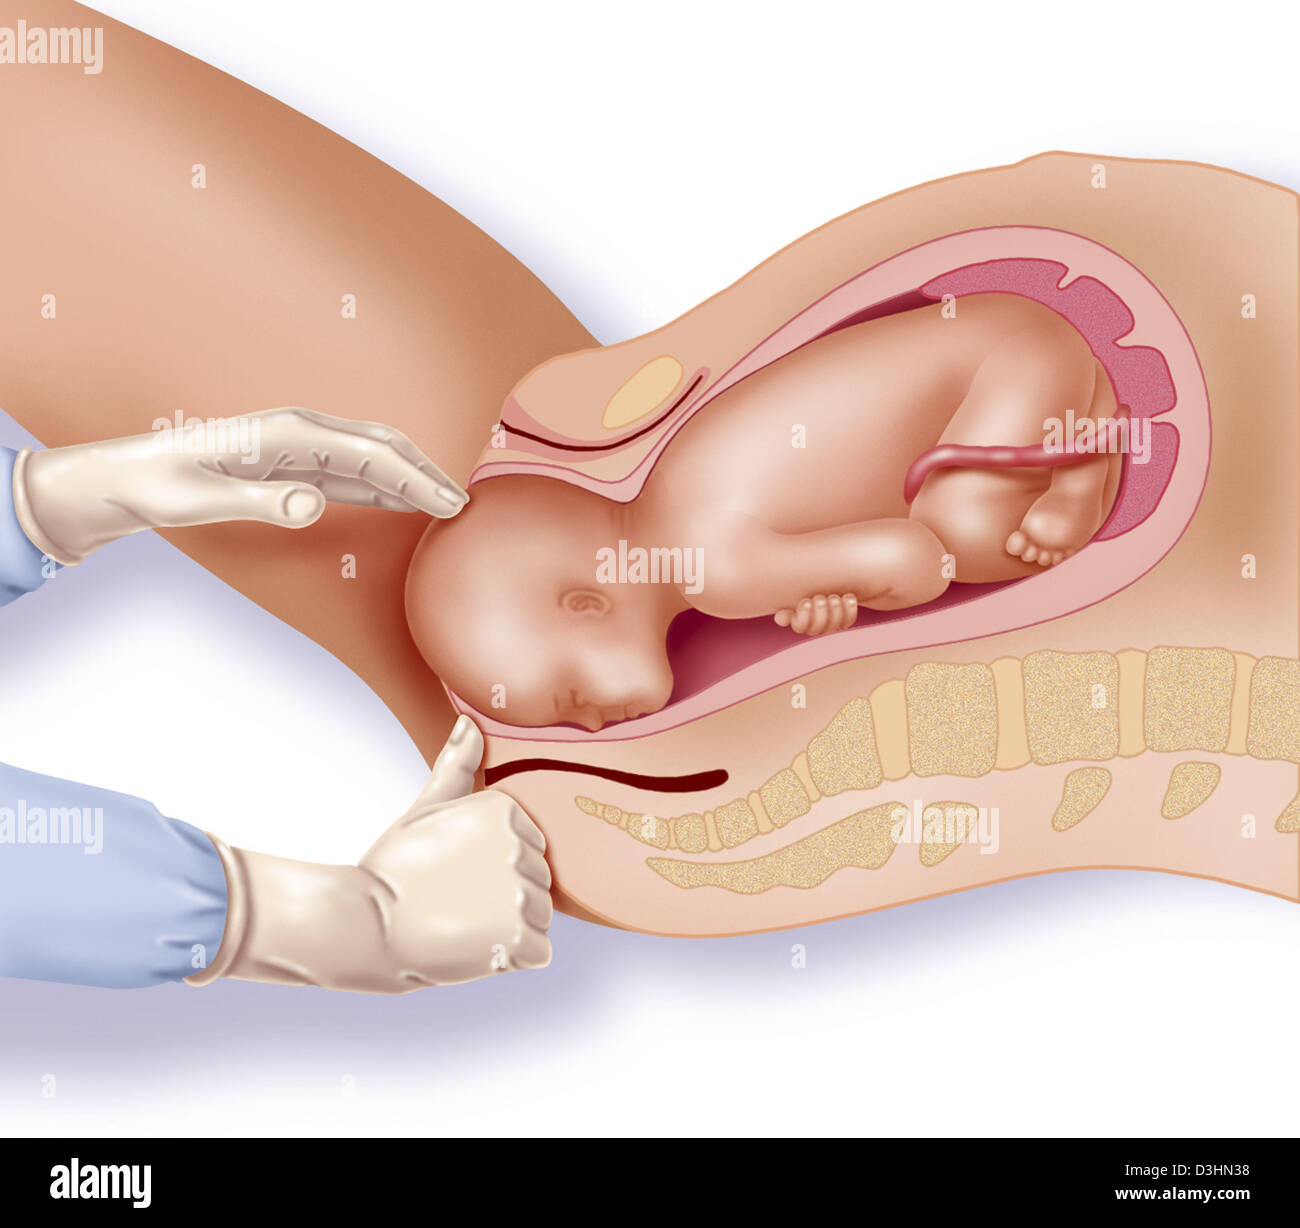

Childbirth, stage 1: the baby is engaged in the pelvis. Stock Photohttps://www.alamy.com/image-license-details/?v=1https://www.alamy.com/childbirth-stage-1-the-baby-is-engaged-in-the-pelvis-image476926081.html

Childbirth, stage 1: the baby is engaged in the pelvis. Stock Photohttps://www.alamy.com/image-license-details/?v=1https://www.alamy.com/childbirth-stage-1-the-baby-is-engaged-in-the-pelvis-image476926081.htmlRF2JKWT29–Childbirth, stage 1: the baby is engaged in the pelvis.